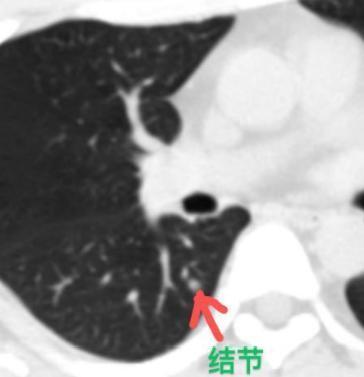

一位29岁的患者,已经做手术切了5个肺结节,左上肺还留着一个7mm肺磨玻璃结节,他吃了整整一年靶向药,结节却一点没缩小! 2年前他体检时,发现肺里长了好几个结节,当时有医生判断这些都是早期肺癌,于是很快就做了手术,一次性拿掉了五个。 术后复查时,发现左上肺还剩下一个很淡的7毫米结节。小伙子很着急,就把之前切下来的结节拿去做基因检测,结果查出来有突变。他就想着,靠吃靶向药把这个剩下的结节“吃”掉。 可惜,药吃了快一年,结节纹丝不动......这次他特地来找我就诊,想问我靶向药还要不要吃下去? 其实,这个肺结节对靶向药并不敏感,也说明,肺里多发的这些结节,虽然都是原发的,但有的带基因突变,有的没有,对药物的反应也各不相同。 我仔细看了他手术前和手术后的CT片子。剩下的那个结节位置长得比较深,而且一直没变化——可能当时医生也是考虑到这个原因,才没有一并切除。 其实,即便当初那几个结节不做手术,我相信到现在也不会有太大变化,因为它们都是很淡的磨玻璃结节。 “越是多发,越要保守”,这句话特别适合用在多发结节的患者身上。定期复查、密切观察,才是更合理的选择。 像这类生长非常缓慢、甚至根本不长的结节,可能十年、二十年,甚至一辈子都保持原样,真的不必急着处理。为了几毫米大、根本不影响生命的东西,切掉一大块肺组织,实在有点得不偿失。 我建议,不如坚持定期复查,如果哪一个结节真的出现变化,我们再针对它进行处理,尽量选在同侧手术,把肺的损伤降到最低。[玫瑰][作揖]胸外科乔贵宾医生MCN双量进阶计划 [心]附:线下免费义诊!11月21日(周五上午),在南方医科大学珠江医院 门诊大厅